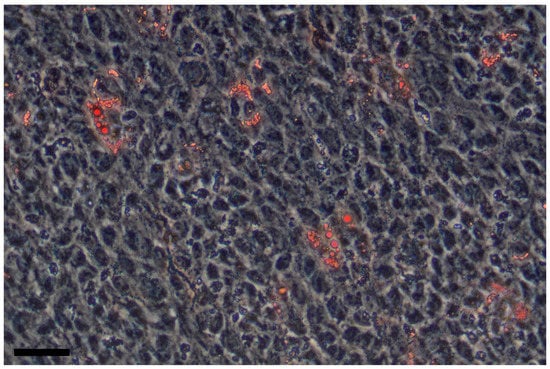

- Herrera, M.B.; Bruno, S.; Buttiglieri, S.; Tetta, C.; Gatti, S.; Deregibus, M.C.; Bussolati, B.; Camussi, G. Isolation and characterization of a stem cell population from adult human liver. Stem Cells 2006, 24, 2840–2850. [Google Scholar] [CrossRef] [PubMed]

- Gerlach, J.C.; Over, P.; Turner, M.E.; Thompson, R.L.; Foka, H.G.; Chen, W.C.; Péault, B.; Gridelli, B.; Schmelzer, E. Perivascular mesenchymal progenitors in human fetal and adult liver. Stem Cells Dev. 2012, 21, 3258–3269. [Google Scholar] [CrossRef] [PubMed]